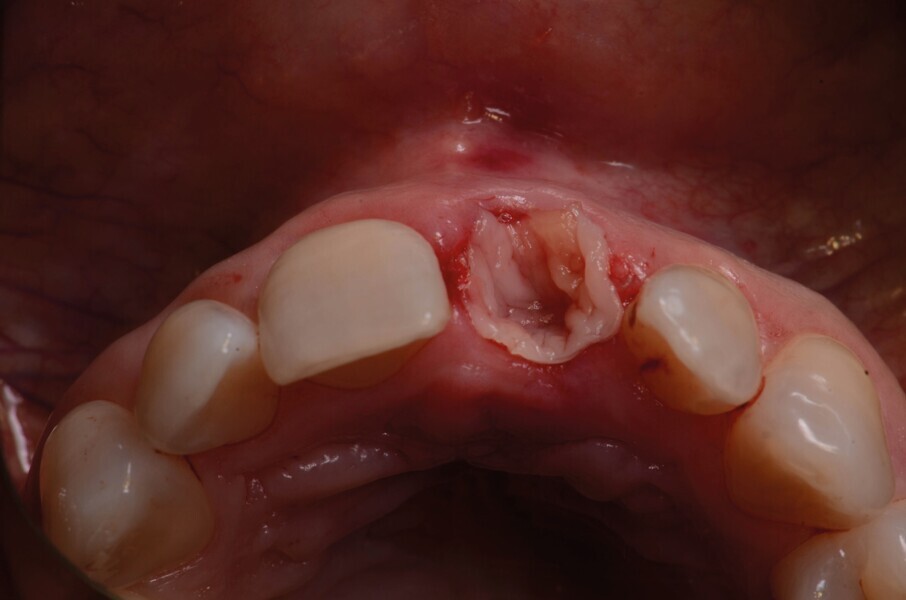

La dent 21 est extraite de la manière la moins traumatique possible à l’aide d’un périotome (Fig. 4). Elle est conservée dans du sérum physiologique afin de pouvoir l’utiliser comme restauration provisoire par la suite.

Fig. 4 : Extraction atraumatique de la dent 21.

Fig. 5a : Après l’extraction

Fig. 5b : Après l’extraction

L’aspect le plus difficile est ici le maintien de l’architecture des tissus mous et des papilles adjacentes. Etant donné la déhiscence osseuse importante, un protocole de préservation alvéolaire est mis en place. L’objectif est de préserver les tissus adjacents et de limiter toute résorption osseuse.